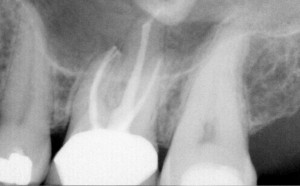

CDR est prêt à capturer des radiographies de haute qualité dès sa première utilisation. La technologie CMOS APS (capteur à pixels actifs) offre des images nettes, à faible bruit et de haute résolution qui montrent les moindres détails pour permettre un diagnostic précis.

CDR est un capteur intra-oral éprouvé qui envoie des images de haute qualité sur votre écran d'ordinateur, nécessitant seulement une fraction du rayonnement émis dans l'imagerie traditionnelle. Le capteur avec son câble ainsi que le câble USB du PC peuvent être détachés du boîtier de commande à distance CDR, permettant une flexibilité et une mobilité totales, et augmentant la sécurité de votre investissement.